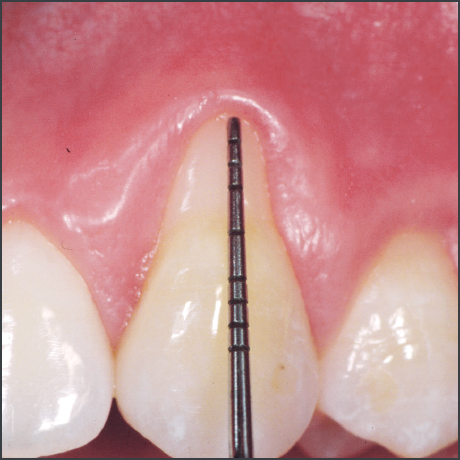

Before treatment with Straumann® Emdogain®.

Courtesy of Prof. Giovanni Zucchelli